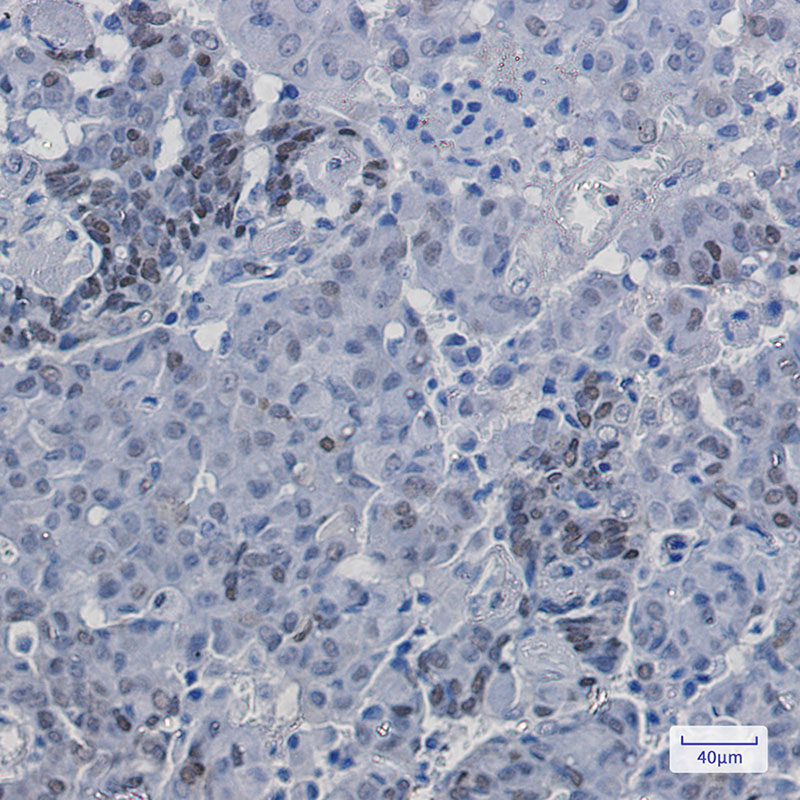

- Immunohistochemistry analysis of paraffin-embedded Human breast cancer using p27 KIP 1 (Phospho-Ser10) antibody. High-pressure and temperature Sodium Citrate pH 6.0 was used for antigen retrieval.